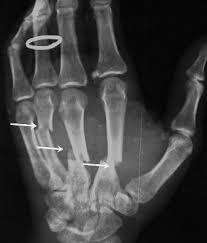

2. POŠKODBE KOSTI:

1. zlomi

1. prečni prelom

1. kominutivni zlom

1. spiralni zlom

1. paličasti zlom